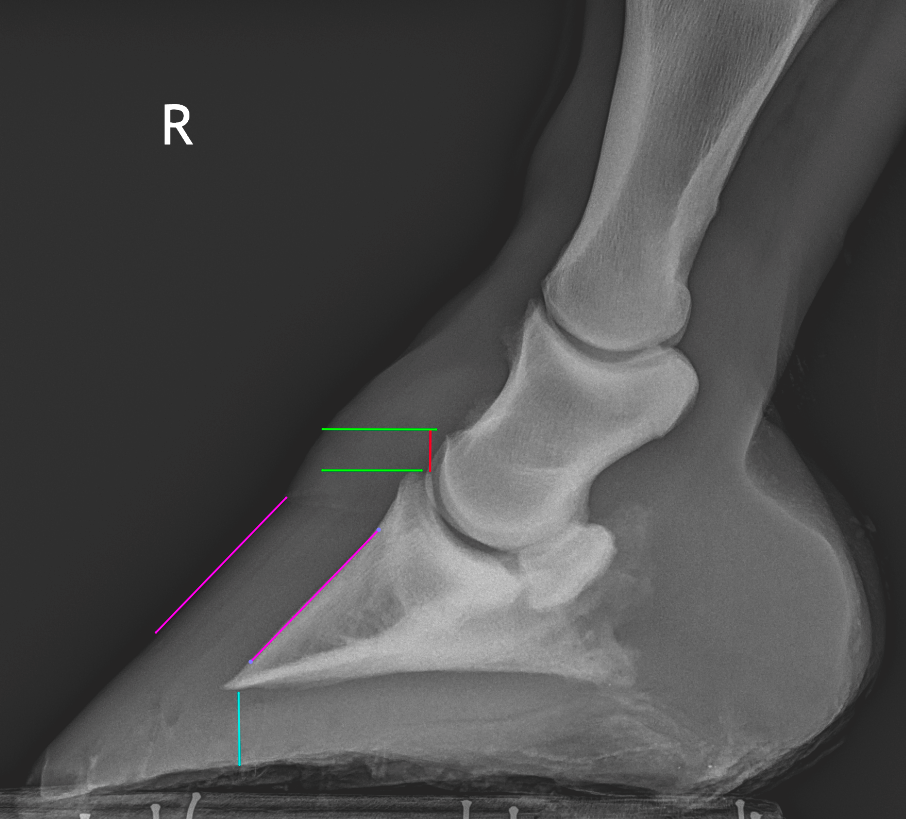

From enlightenedequine.com

Hoof Angles Part 3 — Enlightened Equine How To Help A Laminitic Horse learn about the causes, types, and signs of laminitis, a painful condition affecting the horse's hoof. standing on sand and soaking in ice water are the two things that help severe acute laminitis the most, said van eps. Find out how to prevent and treat laminitis with veterinary and farrier care, dietary management, and supportive therapy. laminitis. How To Help A Laminitic Horse.